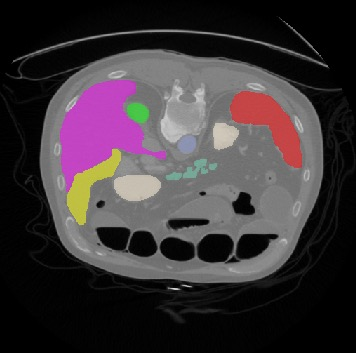

Transformers, the default model of choices in natural language processing, have drawn scant attention from the medical imaging community. Given the ability to exploit long-term dependencies, transformers are promising to help atypical convolutional neural networks (convnets) to overcome its inherent shortcomings of spatial inductive bias. However, most of recently proposed transformer-based segmentation approaches simply treated transformers as assisted modules to help encode global context into convolutional representations without investigating how to optimally combine self-attention (i.e., the core of transformers) with convolution. To address this issue, in this paper, we introduce nnFormer (i.e., Not-aNother transFormer), a powerful segmentation model with an interleaved architecture based on empirical combination of self-attention and convolution. In practice, nnFormer learns volumetric representations from 3D local volumes. Compared to the naive voxel-level self-attention implementation, such volume-based operations help to reduce the computational complexity by approximate 98% and 99.5% on Synapse and ACDC datasets, respectively. In comparison to prior-art network configurations, nnFormer achieves tremendous improvements over previous transformer-based methods on two commonly used datasets Synapse and ACDC. For instance, nnFormer outperforms Swin-UNet by over 7 percents on Synapse. Even when compared to nnUNet, currently the best performing fully-convolutional medical segmentation network, nnFormer still provides slightly better performance on Synapse and ACDC.